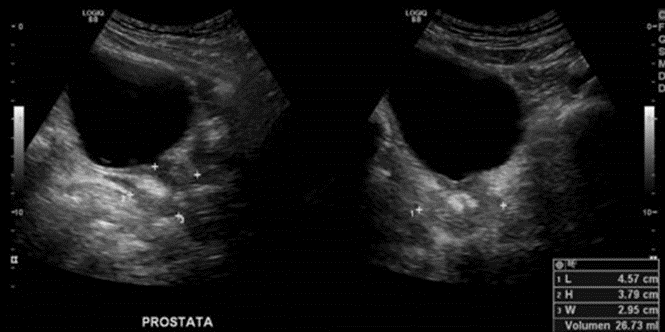

• Volumen prostático aproximado de 26 cm3

Próstata determina un volumen aproximado de 27 cc., con calcificaciones en su espesor.

Vesículas seminales sin alteraciones ecográficas.